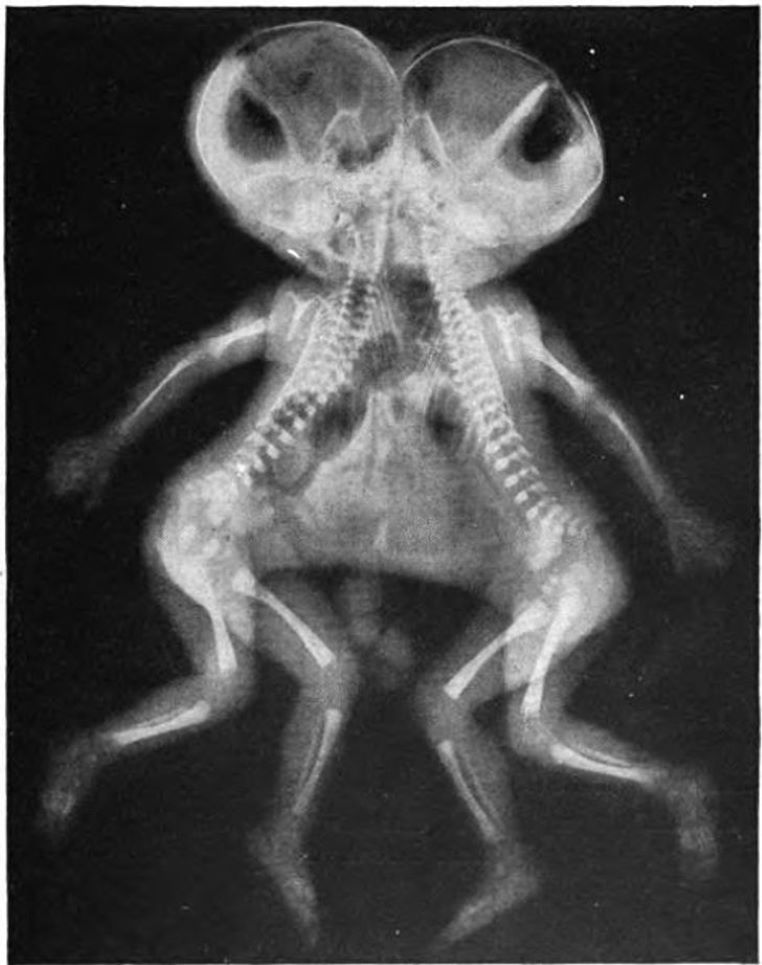

La radiographie des frères siamois !

galerie-rayon-x-frères-siamois